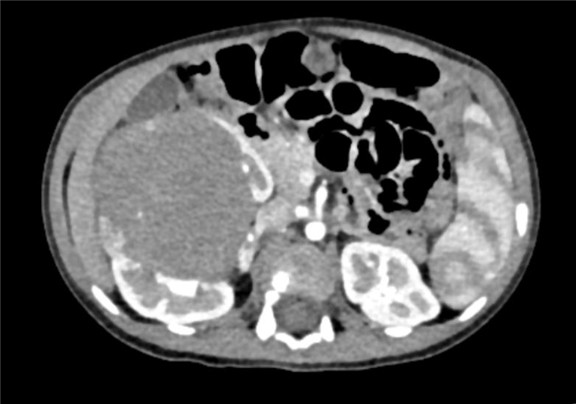

下腹部CT动态增强扫描 肾母细胞瘤化疗后,右肾巨大占位,较前范围减小,请结合临床。

术前CT检查:

动脉期

静脉期

平衡期